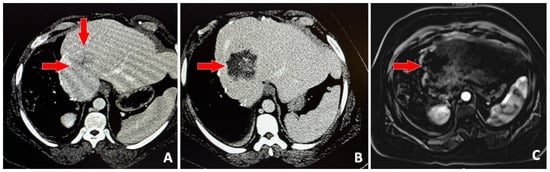

- Vidal-Jove, J.; Serres-Creixams, X.; Ziemlewicz, T.J.; Cannata, J.M. Liver Histotripsy Mediated Abscopal Effect-Case Report. IEEE Trans. Ultrason. Ferroelectr. Freq. Control. 2021, 68, 3001–3005. [Google Scholar] [CrossRef] [PubMed]